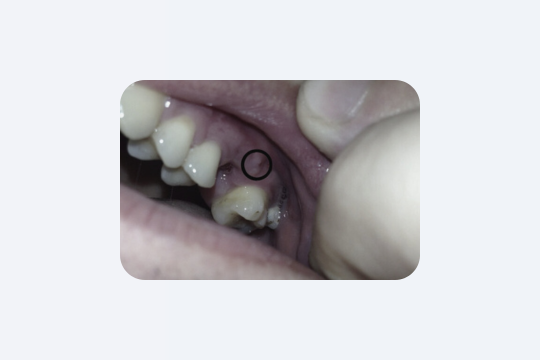

«Бугорок» на дёснах после удаления

Это костная мозоль. Обычно она не вызывает никаких проблем. Её образование связано с травмированием костной ткани во время удаления зуба. Костная мозоль едва заметна, может выглядеть как твёрдая, шероховатая или гладкая шишка на дёснах. Она безболезненна, но может вызывать дискомфорт из-за того, что вы её ощущаете.

В большинстве случаев лечение не требуется, однако в некоторых ситуациях, например при протезировании, врач может порекомендовать её удалить.